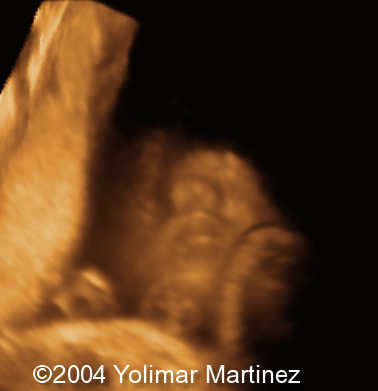

The 3D images

Imagen 28

Imagen 25

Imagen 24